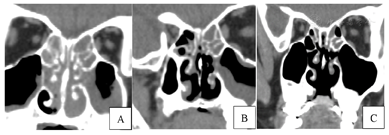

鼻窦CT示双侧上颌窦、筛窦、蝶窦及额窦内黏膜不均匀增厚,鼻甲肿大,鼻腔内异常密度影填充,鼻后孔处显著,软硬腭交界区不规则透亮影,局部软组织缺失(图1A)。

患儿于2022年1月3日及2022年12月22日复查鼻窦CT(图1B、C):预后良好,未见复发情况。